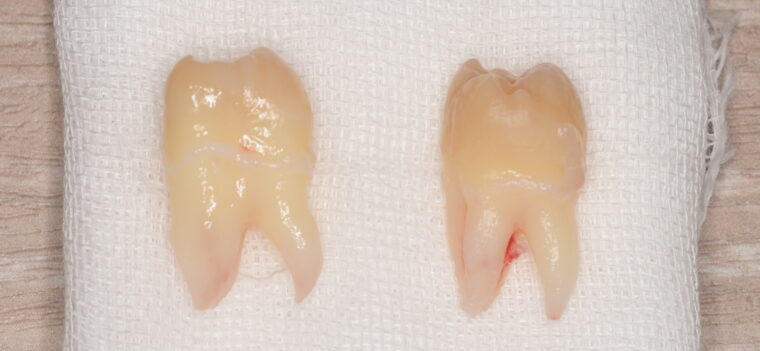

CASE 1

| 親知らずのはえ方 | 完全に出ていてまっすぐはえている |

何度か虫歯になり痛みはないが早めに抜きたい。 完全に頭が出ているため歯ぐきを切ったり骨を削らずに抜歯しました。 根の形も単純なため抜歯自体は5分もかからず上下ともに終わりました。 術後痛みや腫れも出ていません。 抜歯後は感染をしやすいため必ず抗生物質を飲み切ってください。 |